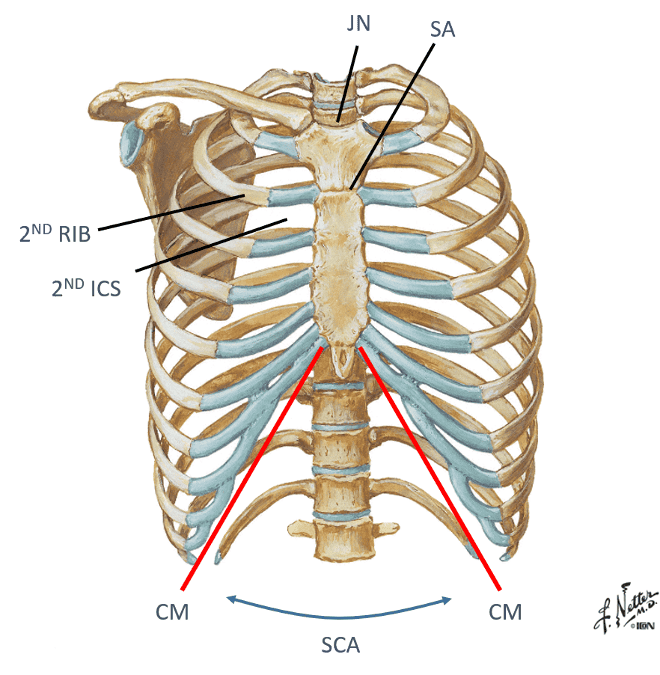

identify:

- Jugular (sternal) notch (JN)

- Sternal angle (SA)

- 2ND rib

- Intercostal spaces (ICS)

- Intercostal spaces 2 - 6

- costal margin (CM)

- subcostal angle (SCA)

look at picture

how do you find and palpate the second rib?

you find the sternal angle ridge on your pt and then feel sideways to feel the ribs and the intercostal spaces...if you move your fingers up and down you can feel the 1st and 2nd rib above and below